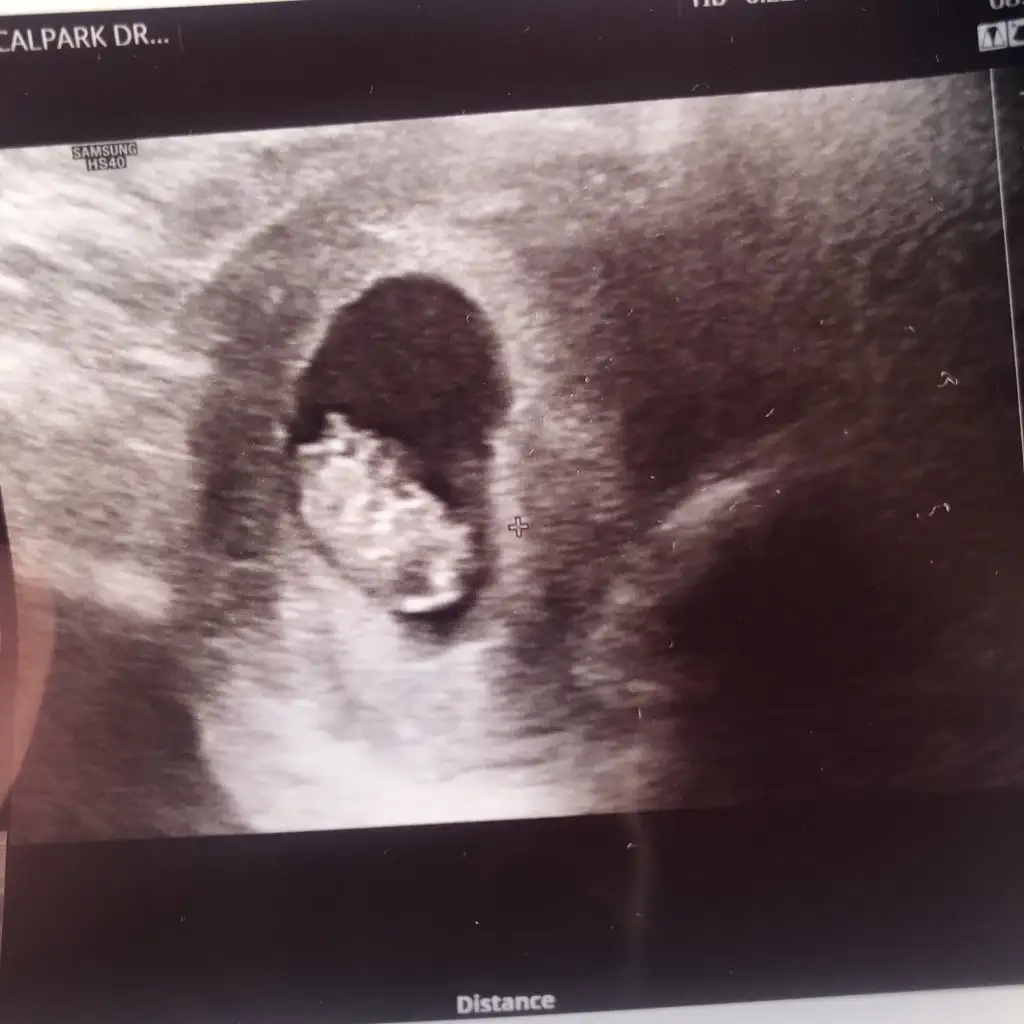

Merhaba 10 ve 8 haftalık görüntümüz tahmininiz nedir ☺️ Teşekkür ederim şimdiden Pasha22 Pasha22

• 4504C141-F0EC-4227-BE4F-02DBFC12A95E.webp

4504C141-F0EC-4227-BE4F-02DBFC12A95E.webp

6,4 KB · Görüntüleme: 238

• AD71A1C7-2C4A-4CF4-AA7A-638A28FAC0FE.webp

AD71A1C7-2C4A-4CF4-AA7A-638A28FAC0FE.webp

11,7 KB · Görüntüleme: 237